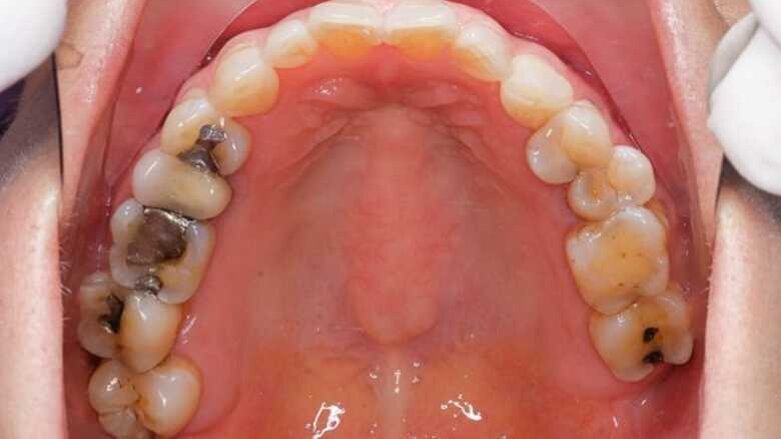

Las restauraciones de amalgama son muy resistentes y su costo, durabilidad y facilidad de manipulación han hecho que sea el material de elección número uno para restaurar dientes posteriores a lo largo de la historia, demostrando ser el mejor de todos, con falencias de tipo estético por supuesto, pero muy completo en muchos otros aspectos.

Las restauraciones de amalgama ocupan un lugar importante dentro de la operatoria dental y son consideradas como uno de los materiales más longevos de los que se dispone actualmente. Sin embargo, las restauraciones estéticas, particularmente las resinas compuestas, han progresado de tal forma que, hoy en día, es posible reconstruir dientes anteriores y reparar molares sin que se note la diferencia con un diente íntegro. Ahora bien: ¿Estamos preparados en Latinoamérica para vivir sin la amalgama dental como material restaurador de bajo costo y alta eficacia?

Las amalgamas dentales se endurecen más rápidamente que otros materiales elaborados a base de resinas, por lo que resultan muy prácticos cuando la obturación debe ejecutarse en áreas cercanas a tejidos blandos o las encías, que no pueden mantenerse secas durante el procedimiento. Debemos tener en cuenta que en la actualidad las amalgamas dentales cada vez se usan menos pero no significa que deban ser erradicadas; su poco uso no solo se debe a temas relacionados con la estética, sino a la polémica que ha generado el hecho de que el mercurio forme parte de la aleación.